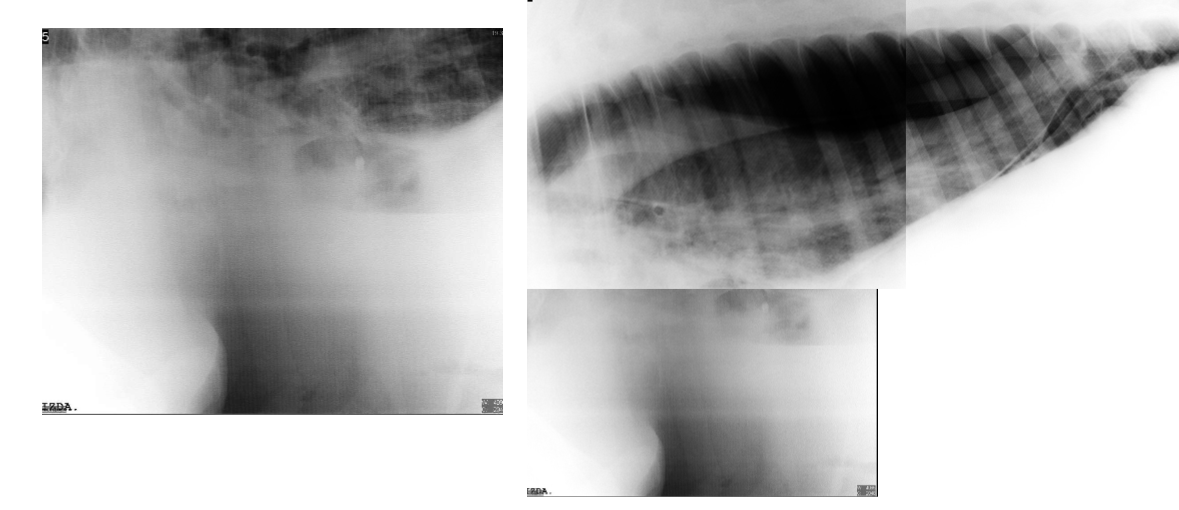

• Bronchoalveolar pattern and a collapsed lung on the RHS due to a pneumothorax

A fluid line on the LHS.